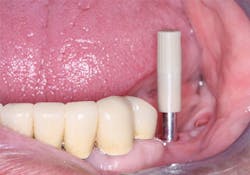

• Often the bone has moderate density and there is some resistance on placement, but loading is still questionable. In such cases, a healing abutment or the final abutment with a provisional restoration on it, both of which should not contact opposing teeth when occluded, can be placed on the implant. These are desirable situations when compared to leaving the implant covered with gingival tissue, since the soft tissue can heal with nearly optimum contour and anatomy while the implant undergoes additional osseointegration. Also, less occlusal force is placed on the implant than if it is loaded immediately. In either of these cases, it is desirable to have the healing abutment or the final abutment slightly wider than the anticipated crown, which allows better access to the implant when a conventional or digital impression is made and more adequate soft-tissue healing in relation to the final restoration.